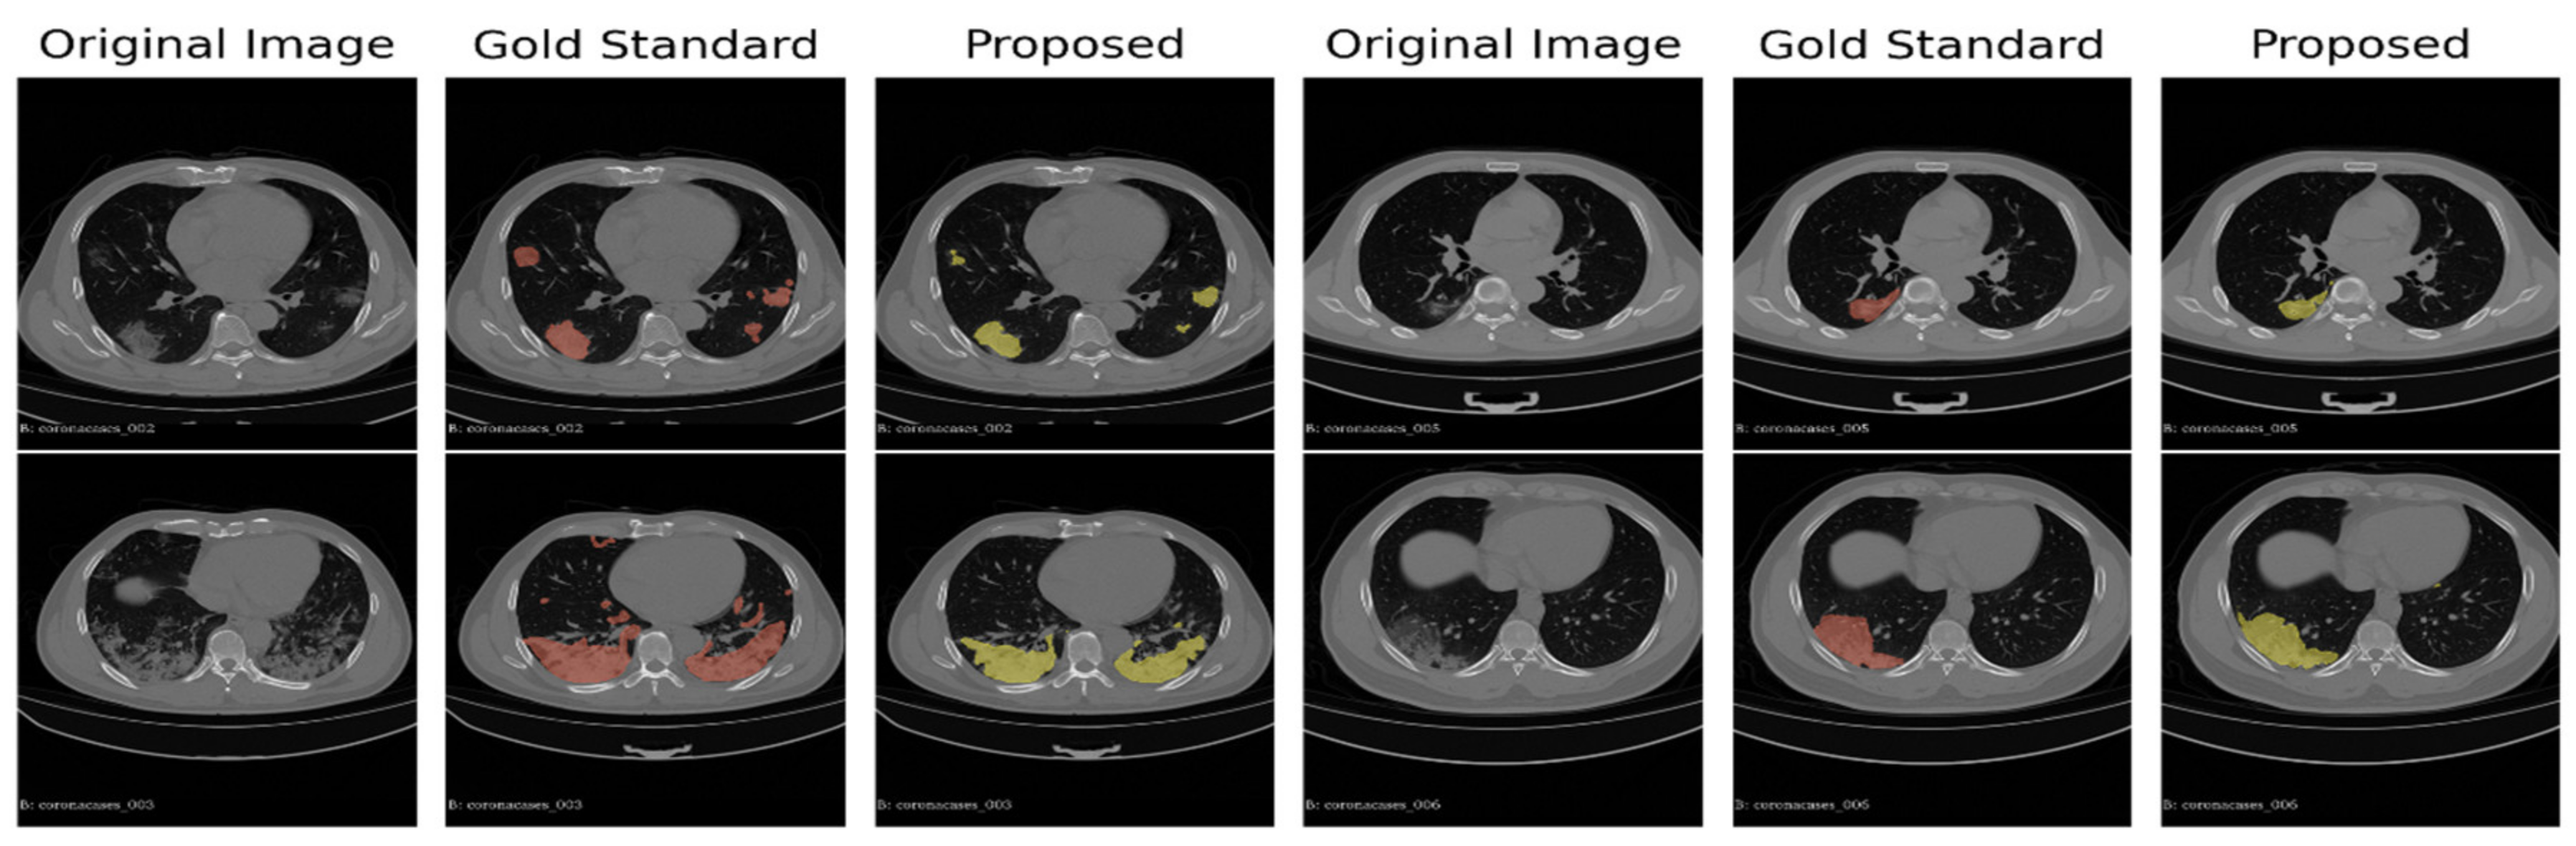

We show in Figure 2 the distribution of the individual scores (Sensitivity, Specificity, Precision, and F1 score). The scores were obtained by the average of the whole 15 scans (overall) on the 10 corona cases (CORONACASES OVERALL) and on the five gold standard (GOLD STD OVERALL). In Figure 3 and Figure 4, we show a visual comparison between the achieved segmentation and the ground truth labels (both for corona cases and the gold standard).

The examples reported in Figure 3 and Figure 4 show how the non-supervised segmentation method proposed in this paper is able to approximate the gold standard results with satisfactory results.

Figure 4. A comparison between the proposed automated segmentation pipeline and a gold standard segmentation manually performed by an expert radiologist.